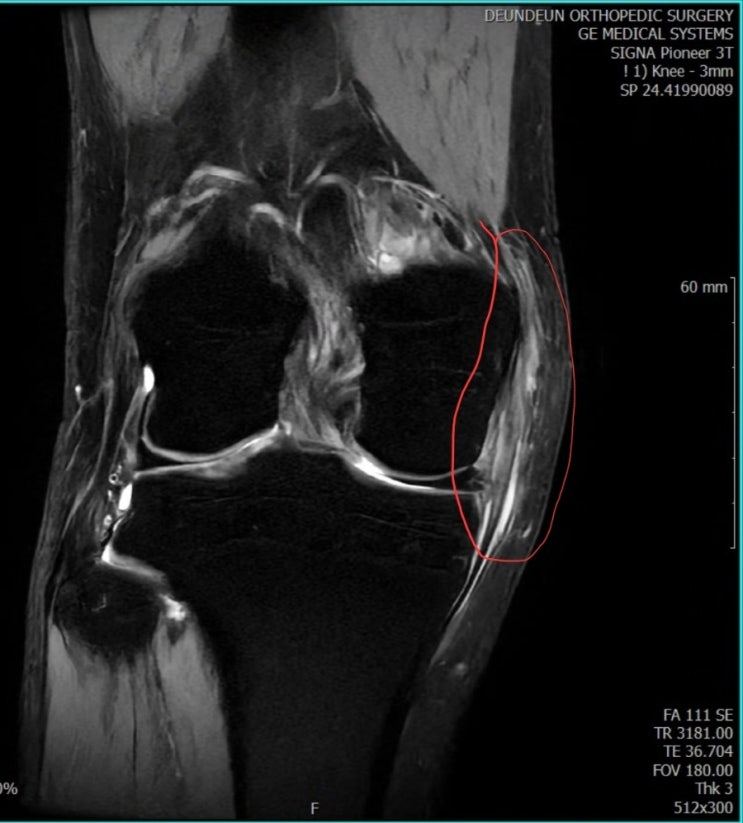

무릎 부상 (feat 든든정형외과)

지난 장마이후 쪽배가 물에 계속 잠겨있어 꺼내야할 상황이였습니다 그런데 경사면을 내려가다가 미끄러지...